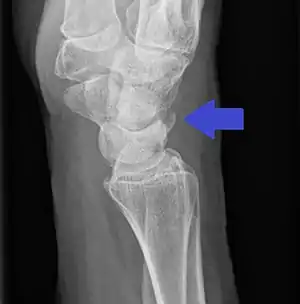

| Triquetral avulsion fracture as seen on lateral X-ray of the wrist | |